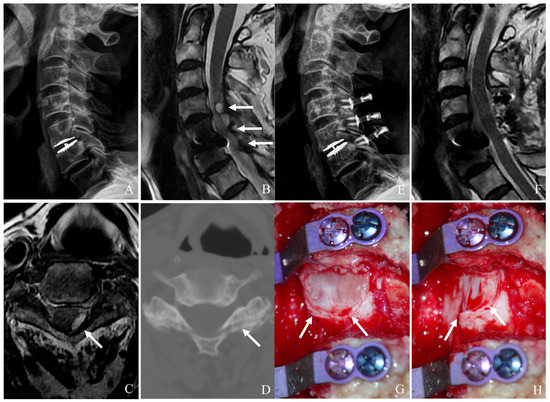

Figure 6. Plain X-rays (A), magnetic resonance image (B,C), computed tomography (D), and clinical photo (G) showing hypertrophy of ligamentum flavum at C4–6 and facet cyst at C4–5 causing cord compression (white arrows). The patient underwent C4accept–6 open-door laminoplasty and removal of facet cyst, leading to complete cord decompression (E,F,H).

6.5. Laminoplasty for ASD After CDA

Laminoplasty is a motion-preserving posterior decompression technique particularly useful for multilevel cervical stenosis without significant instability. It expands the spinal canal while maintaining the integrity of posterior elements (Figure 6A–H) [22,23,24,25,26]. Key indications include the following: